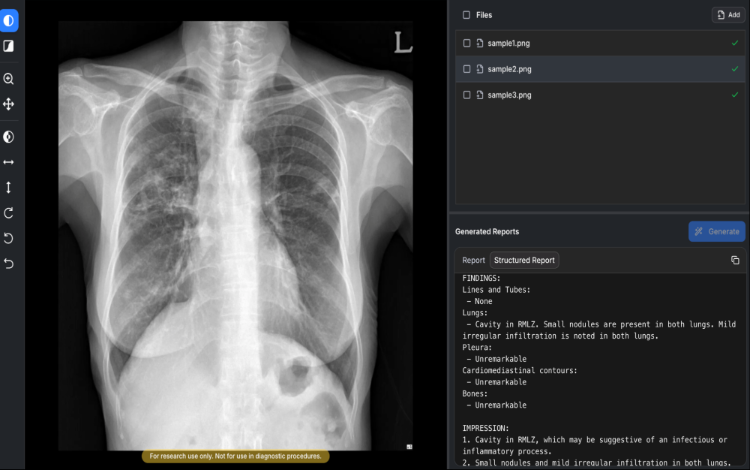

South Korean firm Soombit AI receives Class 3 MFDS approval for AIRead-CXR, a generative AI tool that drafts preliminary chest X-ray reports.

Seoul, South Korea - Medical artificial intelligence company Soombit AI has received Class 3 approval from the Ministry of Food and Drug Safety (MFDS) for AIRead-CXR, a generative AI software that drafts preliminary radiology reports from chest X-rays, the company announced.

The AIRead-CXR model was trained on approximately 14 million domestic and international data points. It processes both posteroanterior (PA) and anteroposterior (AP) chest X-rays.

The software identifies 57 findings and diseases, including cavities, nodules, and infiltrations, and quantifies severity using standardized terminology.

The system synthesizes these imaging findings to provide differential diagnosis information in the impression section of the report.